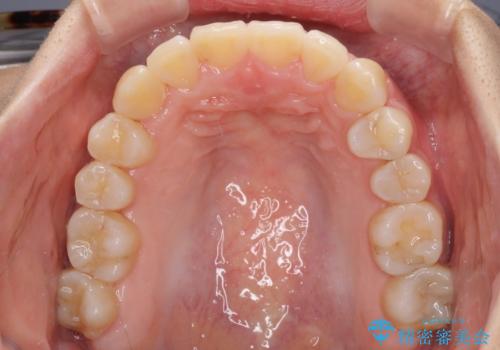

- 前歯のでこぼこと乳歯が残るほどの八重歯を気にして来院された患者様です。

非抜歯にてワイヤー矯正にて治療することとしました。(ただし、親知らずと乳歯は抜歯)

犬歯は歯根が太く長いため、移動には時間を要します。しかし、犬歯は機能面から考えて残すことを選択したいため、長期間をかけて治療を行うこととしました。

治療の度に歯列が改善していったため、長期間の治療も楽しく過ごしていいただき、満足のいく仕上がりとなりました。